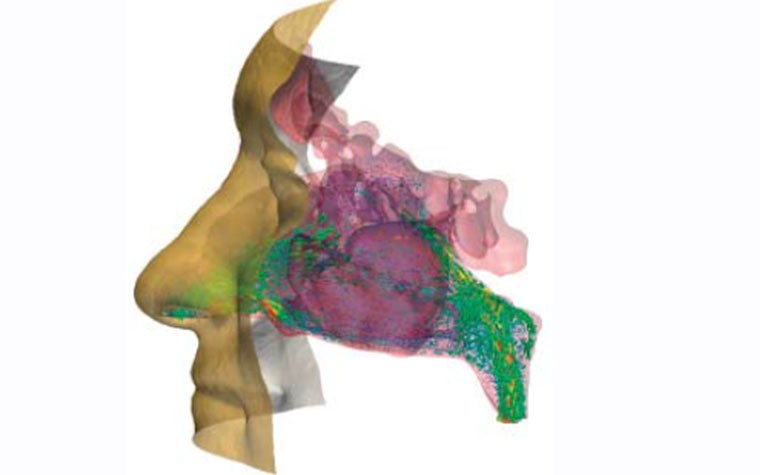

Expirations through the nasal cavity of a European male adult were successfully simulated with OpenLB. The results were validated by comparison with other experimentally and numerically gained results as well as with measurements taken from the patients involved. The visualized simulation results offer new insights into the flow characteristics of human respiration and, for one of the research subjects in particular, the personalized approach helped to locate a stenosis, which is now assumed to be the cause of a severe peripheral obstructive ventilation disorder that had been diagnosed before the study.